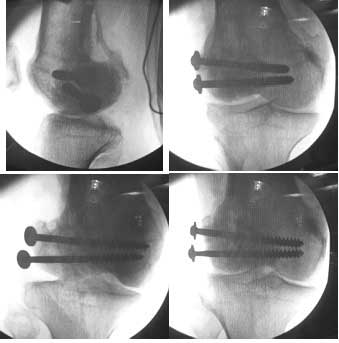

This 20 year old patient sustained a fracture in the lower end of the femur, one and a half years ago, with a compound wound over the fracture area. Notes at that time mention a compound fracture dislocation, with a loss of part of the lateral condyle. This was treated by debridement, and external fixation. After two weeks, the lateral condyle (coronal fracture) was fixed by a screw and k wire in an AP direction.

I opened it up from the lateral aspect.

Freed up the non-union site with minimal disturbance to the posterior and lateral soft tissue attachments on the lateral condyle fragment.

Applied a distractor between femoral shaft and tibia, to create a space on the lateral aspect.

This brought the lateral condylar fragment into a position that seemed to be reasonably well aligned, but showed up a bone gap.

This was fixed temporarily, bone grafted with tricortical struts, and fixed by two cancellous screws. The fragment was not large enough to afford any fixation to a plate or such implant, and the screws held it compressed well to the rest of the distal femur.

Post-op - limb is well aligned, rom 0-30, but I am not pushing that right now, for the next two or three weeks.

Further plan - hope that the screws hold the fragment appropriately till union, but if the stability on table is anything to judge by, that should not be a problem.

Pictures attached.